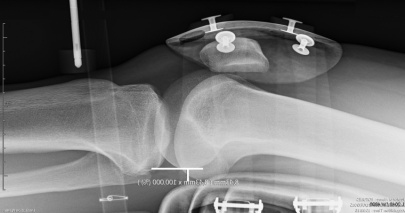

RADIOLOGY

The automated dynamic laximetry for a new approach in the examination of the ligament function

The LDA® allows measurement and calculation of new parameters to enable sometimes complex radiological examinations of the knee ligament function.

The LDA® test is an indispensable complement to medical imaging in the exploration of the ACL. It allows a dynamic vision for the registration of ligament resistance curves.

The GNRB Radio is specially designed for a rational use in a radiology practice

Simple and fast to use, comfortable for the patient (laying on the radiology table), the LDA® test is performed within minutes during the radiological examination.

The GNRB Radio features a 5 seconds lock function of the tibial translation, in the up position, allowing to operate an XRay image.

A patented method of measurement

The Lachmann’s test is fully automated with the GNRB Radio.

The fixation parameters of ankle and tibia are saved. The LDA® software synthesis and compares the measures taken at both knees immediately by measuring the slopes of the ligament resistance curves of the ACL (Innovation Genourob)

Shown example: Preoperative control

Δ 134 = 6 mm, Δ P2 = 2

Complete Rupture

Objectification of a clinical Lachmann-test